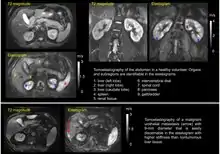

Tomoelastography of the abdomen of a healthy volunteer and a patient

Tomoelastography of the abdomen; upper a healthy state, lower with malignancy.

Tomoelastography requires external driver systems, which can efficiently generate shear waves throughout the entire field of view including tissues deep within the body. Multiple drivers can be combined such that waves propagate from the surface into the body from different directions to enable full illumination of larger regions with shear waves. Tomoelastography often employs mechanical vibrations at several driving frequencies for multifrequency wave analysis in order to stabilize inverse problem solutions for viscoelasticity reconstructions. A standard way of multifrequency viscoelasticity reconstruction is based on phase gradient analysis of plane waves[5] whereas other methods employ solutions of the Helmholtz equation.[6][7][8] The feasibility of tomoelastography was first demonstrated in the human abdomen using multifrequency MRE, where it was possible for the first time to display stiffness values (quantified as shear wave speed in m/s) across the entire axial MRI slice.[5] Although the elastograms are quantitative maps, tomoelastography images, like other radiological images, are often presented in standard gray-scale which gives more perceptual contrast to the subtle nuances than the color-scale.

Currently, most applications of tomoelastography are based on MRI, which is why tomoelastography is often referred to as an advanced MRE technique. Multifrequency-MRE based tomoelastography has been used for the diagnosis of diffuse liver disease,[9][10][11] renal diseases such as renal allograft dysfunction,[12] lupus nephritis,[13] and immunoglobulin A nephropathy (IgAN).[14] In addition, tomoelastography has been used for cancer imaging. In the liver, viscoelastic parameters of lesions less than 1 cm in diameter could be quantified for diagnostic purposes.[15] Pancreatic cancer has been shown to be abnormally stiff compared to surrounding tissue, resulting in a large tumor contrast in elastograms.[16][17] In the prostate, tomoelastography has been able to distinguish cancer from benign lesions.[18]